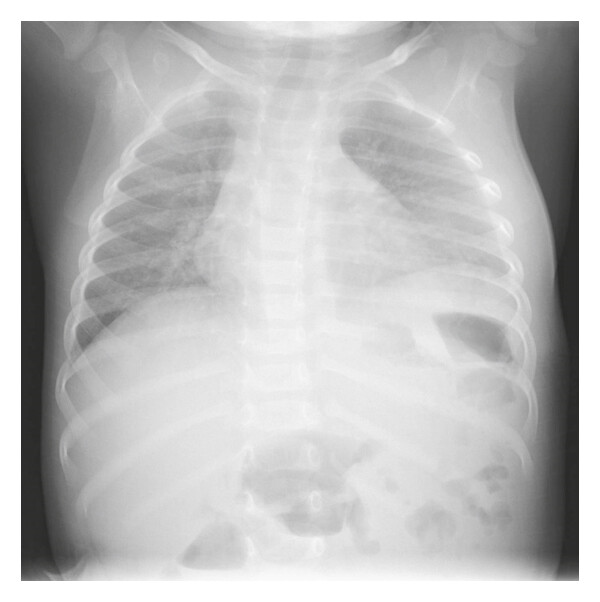

Инструментальные методы диагностики включают рентгенографию грудной клетки, однако на ранних стадиях костные изменения могут быть минимальными или отсутствовать. Рентгенологическая диагностика остеомиелита рёбер направлена на выявление прямых признаков воспалительно-некротического процесса в плоских костях грудной стенки, включая деструкцию кортикального слоя и перестройку губчатого вещества. Исследование проводится в прямой и косых проекциях в режиме обзорной рентгенографии с прицельной съёмкой поражённого сегмента грудной клетки.

Рентген выявляет следующие анатомические признаки:

- В прямой проекции визуализируется участок остеопороза в теле ребра с нарушением обычного трабекулярного рисунка, размытыми контурами и снижением плотности в зоне предполагаемого воспаления.

- В косой проекции определяется прерывистость наружного кортикального слоя с деформацией изгиба ребра и признаками периостального наслоения, образующего неравномерную теневую полосу вдоль диафиза.

- На прицельной рентгенограмме отмечается наличие секвестра — отдельного фрагмента плотной костной ткани внутри зоны остеолиза, окружённой зоной склерозирования и возможного периостального отслоения.

Рентгенографическое исследование позволяет детально визуализировать следующие диагностические параметры остеомиелита рёбер:

- Протяжённость и локализация зоны остеодеструкции, включая вовлечение диафизарной и паракостальной части ребра.

- Форма, размеры и плотность секвестра, позволяющие отличить зону некроза от реактивных костных изменений.

- Степень нарушения кортикального слоя и выраженность периостальной реакции с определением её распространения и конфигурации.

- Наличие склеротической каймы вокруг очага воспаления, отражающей стадию хронического процесса.

- Сопоставление положения очага с соседними анатомическими структурами грудной клетки, включая мягкие ткани.

Рентгенологическое обследование ребер имеет ряд ограничений, и с его помощью не всегда удаётся точно визуализировать следующие аспекты:

- Начальные воспалительные изменения без деструкции костной ткани могут не проявляться в течение первых 10–12 суток.

- Слабовыраженные перестройки в губчатом веществе рёбер при поверхностном распространении инфекции могут быть неразличимы на фоне плотности грудной стенки.

- Оценка состояния прилежащих мягкотканевых структур, включая мышечную и жировую клетчатку, недоступна в рамках проекционного метода.

- Интраструктурные гнойные полости и небольшие каналы секвестрации остаются за пределами визуализации при стандартных режимах съёмки.

- Присутствует лучевая нагрузка: при выполнении рентгенографии грудной клетки в прямой и косых проекциях с прицельной съёмкой поражённого ребра суммарная эффективная доза составляет от 0,2 до 0,5 мЗв.

Более информативной является компьютерная томография ребер, позволяющая визуализировать участки остеолиза, секвестрации, периостальную реакцию, разрушение кортикального слоя рёбер и наличие парарёберных абсцессов. Магнитно-резонансная томография грудной клетки позволяет оценить распространение воспалительного процесса на мягкие ткани, визуализировать отёк костного мозга, свищевые ходы и области инфильтрации. В хронических случаях возможно применение остеосцинтиграфии с технецием-99m для определения метаболически активных очагов воспаления.